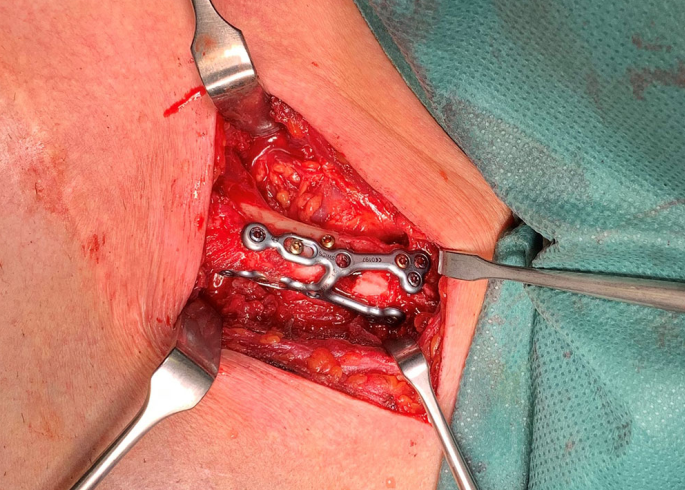

步骤一:常规锁骨内侧横行切口,分离暴露锁骨内侧端骨折,临时复位、克氏针固定。

步骤二:桡骨远端背侧钢板(2.5mm,瑞士Aptus),塑形后呈“H”形,双臂呈90°。